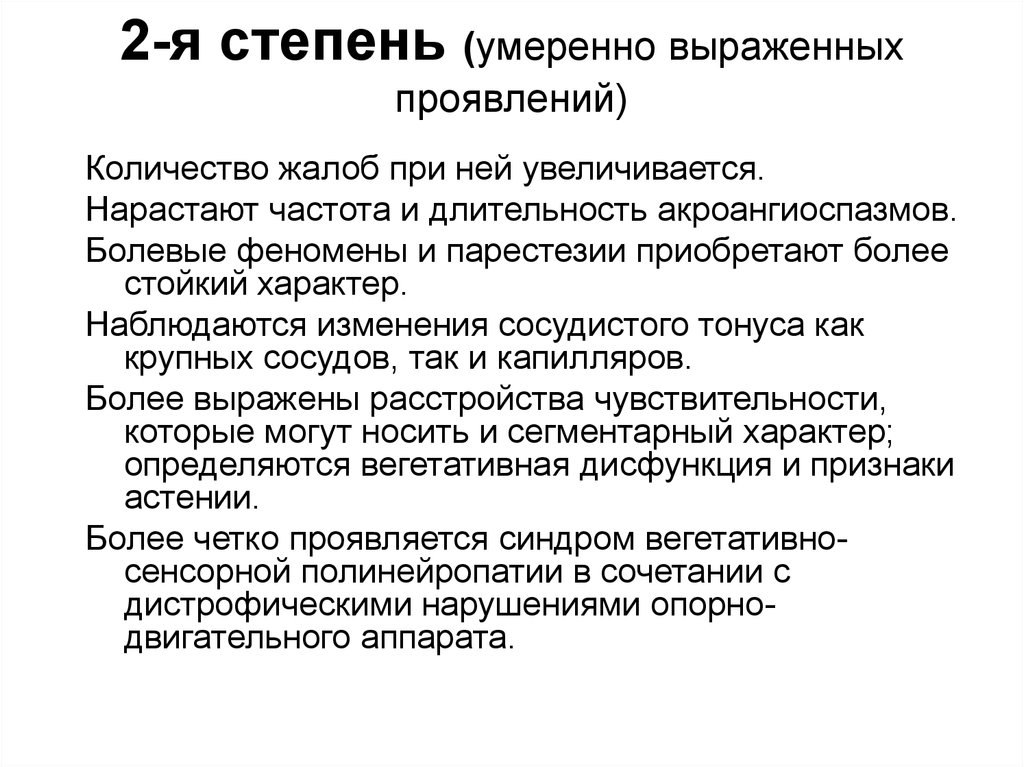

Признаки умеренно выраженной наружная

Признаки умеренно выраженной наружная 113 фото